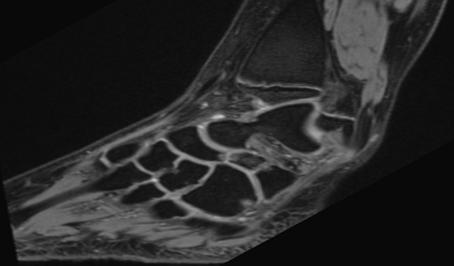

A 16-year-old female, who had presented with repeated left ankle sprains over several years, was consulted at our emergency room for a new left ankle sprain. Radiological evaluation (X-ray and MRI) revealed a discrete oedema of the calcaneal rostrum, with a 4-mm bone fragment between the calcaneum and the navicular bone, making clinicians suspect an avulsion fracture. The talonavicular, spring and bifurcated ligaments were normal. A complementary computed tomography (CT) scan confirmed a 2.8 x 4.5-mm bone fragment with a partially cortical appearance (Figure 1). Treatment was a plaster splint for four weeks. Despite physiotherapy, pain and limited mobility continued, and the patient described pain when walking on non-flat surfaces. On palpation, there was elective pain on the anterolateral side of the mid foot and subtalar motion was restricted. Clinicians proposed a surgical exploration using a lateral approach. We noted synchondrosis/synfibrosis between the calcaneal body and the anterior calcaneal process and between an OCS and the navicular bone. A surgical excision of the OCS was performed, and the extensor digitorum brevis muscle was interposed in the gap left by the removal of the bony piece. At nine months, the patient was walking without pain, had no further sprains and her subtalar motion was no longer restricted.

Figure 1: Computed tomography scan image of a partially cortical bone fragment located between the calcaneus and the navicular bone.